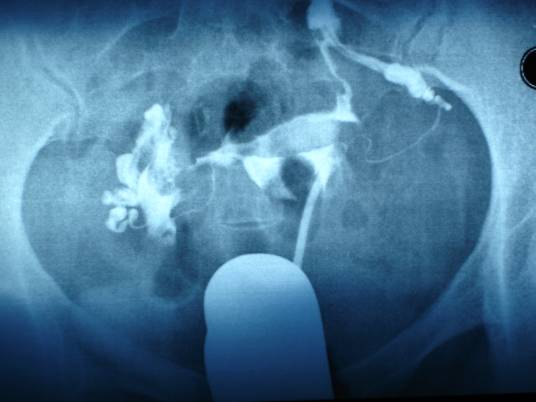

输卵管造影术是经X线的子宫输卵管造影是通过导管向宫腔及输卵管注入造影剂,利用X线诊断仪行X线透视及摄片,根据造影剂在输卵管及盆腔内的显影情况来了解输卵管是否通畅、阻塞部位及宫腔形态的一种检查方法。

造影前排清大小便,消毒外阴、阴道和宫颈。在无菌操作下抽出造影剂7~10ml,因导管内须容纳2ml,宫腔内约容3~5ml。将金属导管或双腔导管插入宫颈内阻紧。排出导管中气泡,以防误诊为息肉或肌瘤。在透视下边注入边观察,至子宫输卵管均充盈即撮片;或在不透视下缓慢注入,至病人下腹胀即摄片。如果注入时有明显阻力感或病人疼痛难受时,应停止注射,总注入量约5—10mi。如注入碘水剂,则连撮2片,相隔lO~15min,若注入碘油剂,第l片洗出观察后,酌情摄第2片,待24小时后,擦洗阴道,清除可能残留在阴道内的碘剂,再摄盆腔平片一张。若输卵管通畅,则输卵管内无油剂残留,进入盆腹腔的油剂呈涂抹状影像,子宫腔内残留呈纵行条状影,阴道内呈横行条状影,输卵管伞部残留呈香肠状影。

(3)若应用金属导管将造影剂充满导管,排尽空气,而后将导管插入子宫颈,堵紧宫颈外口,不至使造影剂外溢,在X线透视下观察造影剂流经宫腔及输卵管情况并摄片。在这个时期最好要摄片两张,第一张掌握在造影剂充满子宫及输卵管全程的时候,造影剂经输卵管进入盆腔内一少部分时摄第二张,如造影剂进入盆腔内弥散过多拍第二张,由于造影剂进入盆腔内弥散将影响对输卵管具体情况的准确观察,而后再次注入一定量的造影剂,顺便拔出导管后让患者适当走动,20分钟左右待造影剂在盆腔内充分弥散时拍最后一张延迟造影片。若应用气囊导管进行造影其过程和金属导管造影过程大体相同。须要注意的是在进行子宫输卵管造影检查过程的拍片的抓拍时机,一定要掌握在造影剂流经输卵管,保持一定压力在造影剂流动的过程中拍片,只有这样才能清楚的了解管腔的具体通畅情况。

2、在X线透视下观察造影剂流经宫腔及输卵管情况并摄片。在荧光透视下徐徐注入碘油。注入量第一次为3~5ml,观察其进入子宫及流经输卵管的情况,此时摄片一张。继续推入碘油3~5ml,5~10分钟后拍片。

4、收缩或输卵管痉挛,可针刺合谷、内关穴或肌注药品,24小时再在同样部位拍摄第三张片,观察腹腔内有无游离的碘化油。见边界清楚的碘团,则考虑输卵管粘连。输卵管粘连堵塞有轻有重,粘连共分三度,输卵管峡部粘连为一度:输卵管与宫角结合部粘连为二度;输卵管壶部与伞口粘连为三度。